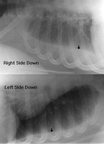

B-cell lymphomas in the immunodeficient host can appear in many parts of the body including the mediastinum, pleura, CNS (both brain and spinal cord), and abdominal and mesenteric chain. In the lung, they tend to spread extensively and may result in respiratory failure. In some cases, they do not spread in the lung and remain as solitary nodules. In immunocompetant individuals, EBV-associated lymphomas have occured in the brain.